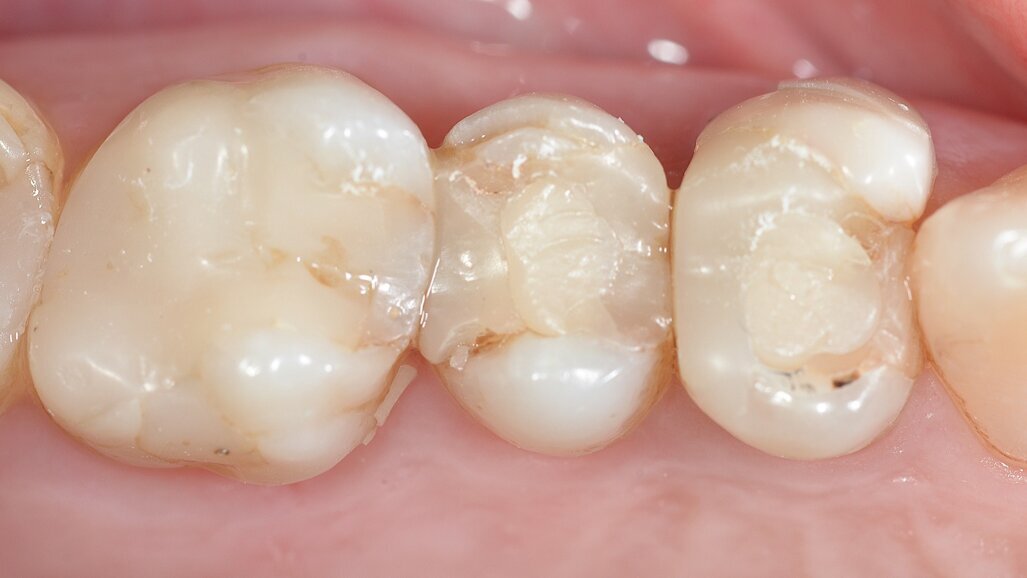

Dopo un ritrattamento canalare (Fig. 2) dei due premolari e un dente ricostruito con perno-moncone fuso (Fig. 3), sono stati posizionati due provvisori.

Fig. 3: Denti preparati per l’impronta digitale.